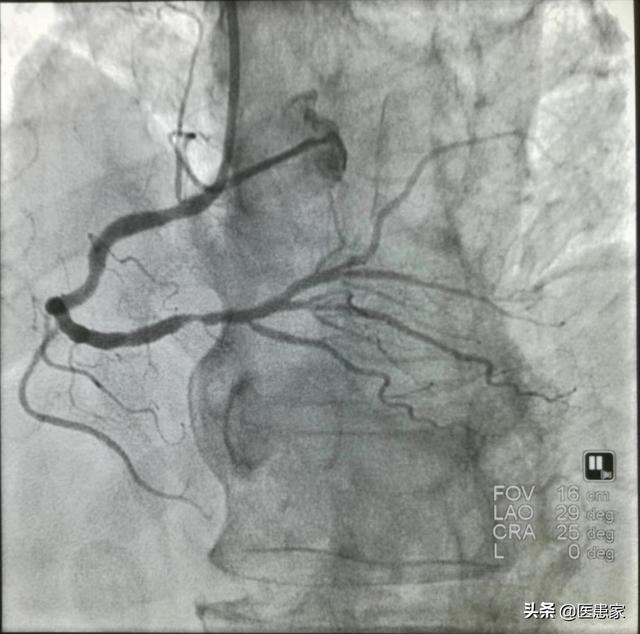

Un cardiogramme, ou plus précisément une coronarographie, est un examen qui permet de déterminer la présence de plaques d'athérome sur les parois des vaisseaux sanguins (artères coronaires) qui alimentent le cœur en sang. Si c'est le cas, quel est le degré de rétrécissement de la lumière des vaisseaux sanguins, afin de déterminer s'il y a une maladie des artères coronaires, ce qui est l'étalon-or pour le diagnostic de la maladie des artères coronaires.

1, le médecin fait une ponction dans l'artère de la main droite du patient et y introduit une gaine, qui est la base de tout.

2, le cathéter de contraste est acheminé vers le cœur à travers la gaine.

3. L'agent de contraste est injecté par un cathéter de contraste et visualisé extérieurement par une radiographie.

Le changement pathologique de la maladie coronarienne est le rétrécissement de l'artère coronaire dû à la formation d'une plaque d'athérome dans l'artère coronaire. En général, une sténose de l'artère coronaire de plus de 50 % peut être diagnostiquée comme une maladie coronarienne. Le diagnostic de sténose de l'artère coronaire peut être établi par le scanner coronaire et la coronarographie, et l'électrocardiographie peut être utilisée comme test auxiliaire pour l'ischémie myocardique. Parmi ces examens, la coronarographie, qui est l'"étalon-or" du diagnostic des maladies coronariennes, est plus précise. Cependant, comme la coronarographie est un examen invasif qui comporte certains risques et qui est coûteux, de nombreux patients la rejettent.

La coronarographie est l'indice de référence pour le diagnostic de la maladie coronarienne. Outre son rôle diagnostique, elle peut également guider le traitement, en particulier lorsque la nécessité d'une thérapie interventionnelle doit être réalisée par coronarographie.